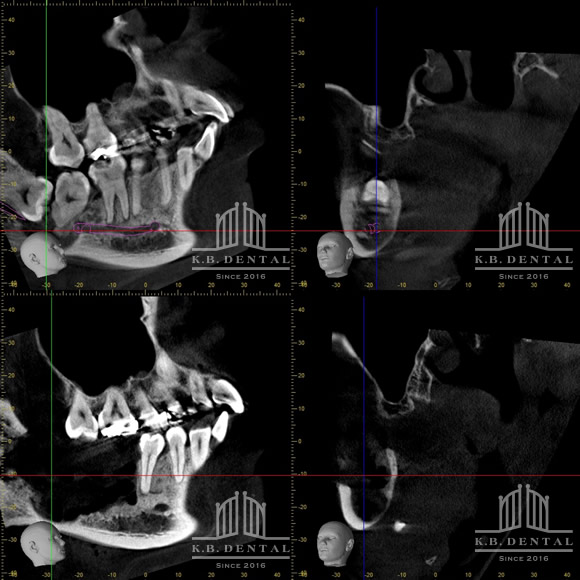

術後2年経過の最も典型的なエナメル上皮種です。再発率が非常に高いので最低でも5年以上の経過観察が必要となります。今回は摘出術と一部健常域まで辺縁切除(骨を削る)を行いました。

2枚目(CT)上:術前 下:術後 摘出部分に新生骨を認めます。